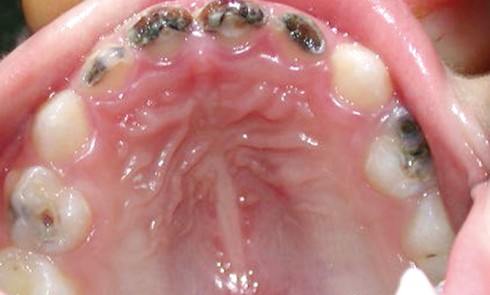

Article réservé à nos abonnés Carie précoce du jeune enfant

Malgré les progrès de prévention de la maladie carieuse, il est encore fréquent de recevoir en consultation d’odontologie pédiatrique de...